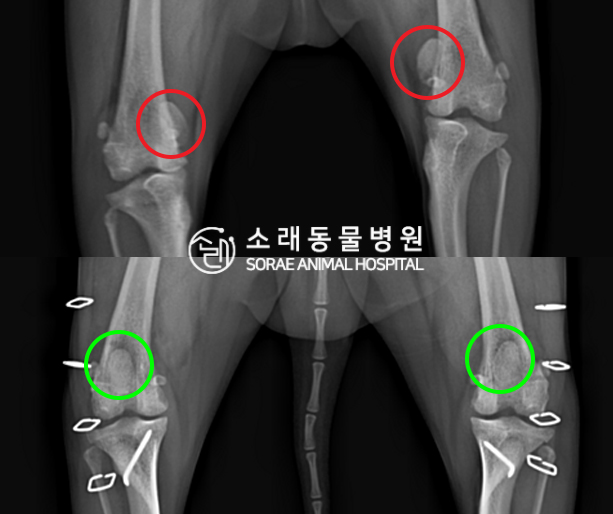

수술전과 수술후에 촬영한 건성이의 슬개골

방사선 사진입니다. 나란히 놓고 비교해보니

슬개골의 위치에 확연한 차이가 있는 것을

확인해 볼 수 있는데요. 내측으로 탈구되어 있던

슬개골이 원래 제자리인 활차구에 예쁘게

자리 잡고 있는 모습을 확인할 수 있었습니다.